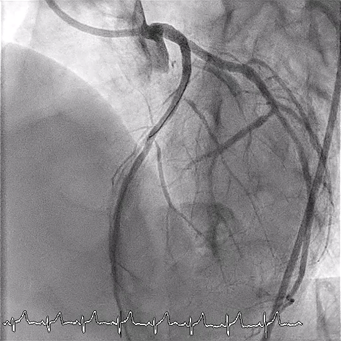

Real-time intravascular ultrasound (IVUS)-guided wiring of the LAD was then planned. An AltaView IVUS catheter (Terumo) was placed at the LCx wire. The IVUS lens served as a landmark for the ostial LAD. A Gaia Next 1 wire (ASAHI INTECC) supported by a single-lumen HighTrack microcatheter (Terumo) was then used to wire the ostial LAD (Figure 2). The Gaia Next 1 wire successfully crossed the ostial LAD lesion, as confirmed by IVUS (Figure 3). It was subsequently exchanged for a Gaia Next 2 (ASAHI INTECC) wire through the microcatheter to address another tight lesion in the proximal LAD. The procedure was completed successfully following balloon dilatation and stenting (Figure 4). The total amount of contrast use was 35 mL.